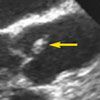

A subsequent transesophageal echocardiogram revealed a mobile mass of about 9 × 4 mm attached to the aortic valve (A). In addition, intravenous injection of agitated saline suggested a patent foramen ovale (PFO), with bubbles freely traversing the interatrial septum from right atrium to left atrium (B).